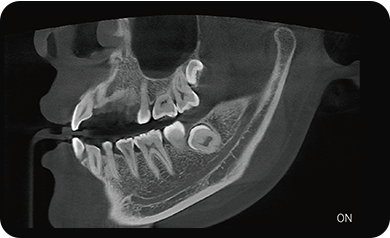

局部超清显示、 移动视野摄片

可根据临床需求任意调整成像区域大小实现局部超清三维显示

临床样片